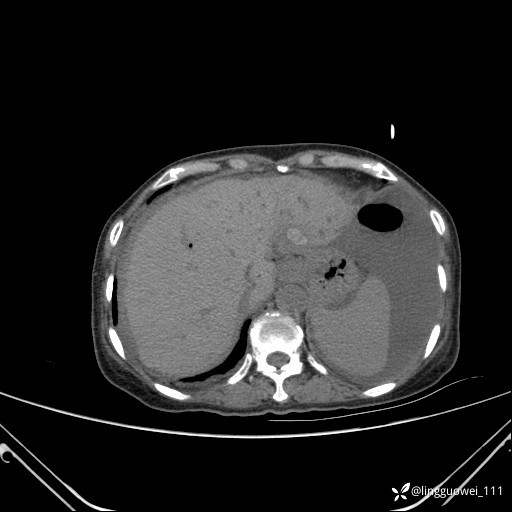

主诉:门诊行胃肠镜检查后,诉腹胀,入院检查,肝有病变吗?腹膜及腹腔的表现有特征性吗?

平扫: